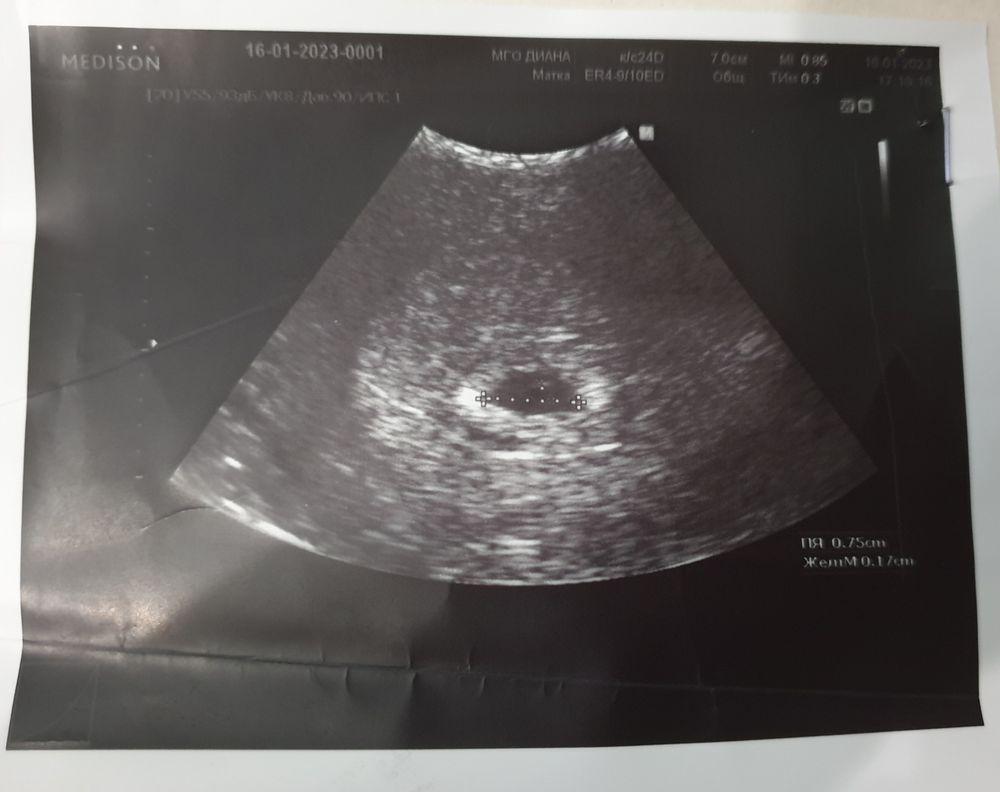

Здравствуйте, хочется послушать Ваше мнение по поводу даты зачатия, ПМ с 12.12.22 по 16.12.22, тест положительный 2 полоски 9 января, 11 Января clear blue digital показал 2-3, УЗИ вот от 16 января, ПЯ 7,5 мм.

Belko, Ну через 16 дней на узи можно увидеть плодовое яйцо 7,5 мм?